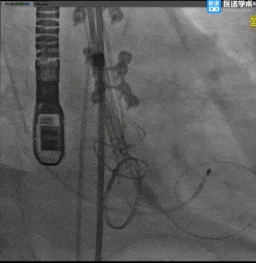

TaurusElite®最终释放形态

术后评估

主动脉瓣术后平均压差7mmHg,无瓣周漏。

对本例手术,修建成教授团队通过术前详尽的检查分析评估,对可能发生的各种突发情况进行充分预估,并准备了相应的应对预案,手术中采用左前斜头位体位,较高位释放(0-2mm),术后跨瓣压差降至7mmHg,血流动力学得到有效改善,为患者带来更长久的生存预期和更高的生活质量。本例手术的成功开展再次展现了修建成教授团队在诊治高难度复杂主动脉瓣膜疾病的雄厚实力和丰富经验,为临床上解剖异常、情况复杂的患者行TAVR治疗提供了更多的参考,也为外科生物瓣膜毁损后的老年高危心脏瓣膜病患者的治疗提供更多的信心!